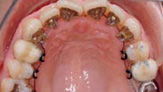

• 舌侧正畸

将托槽等装置粘贴在内侧,在治疗过程中,外观上看不到托槽等牙齿矫正治疗装置。舌侧正畸均由贝臣正畸医生亲自操刀,矫正器均送往德国精加工,因此矫正效果高效显著。